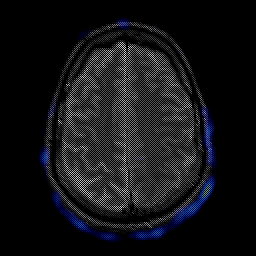

glioma overlay -- Slice #21

[Home][Help][Clinical] Slice 21

Click on sagittal image to select slice. Click on thin tickmark to change timepoint, or thick tickmark for overlay.